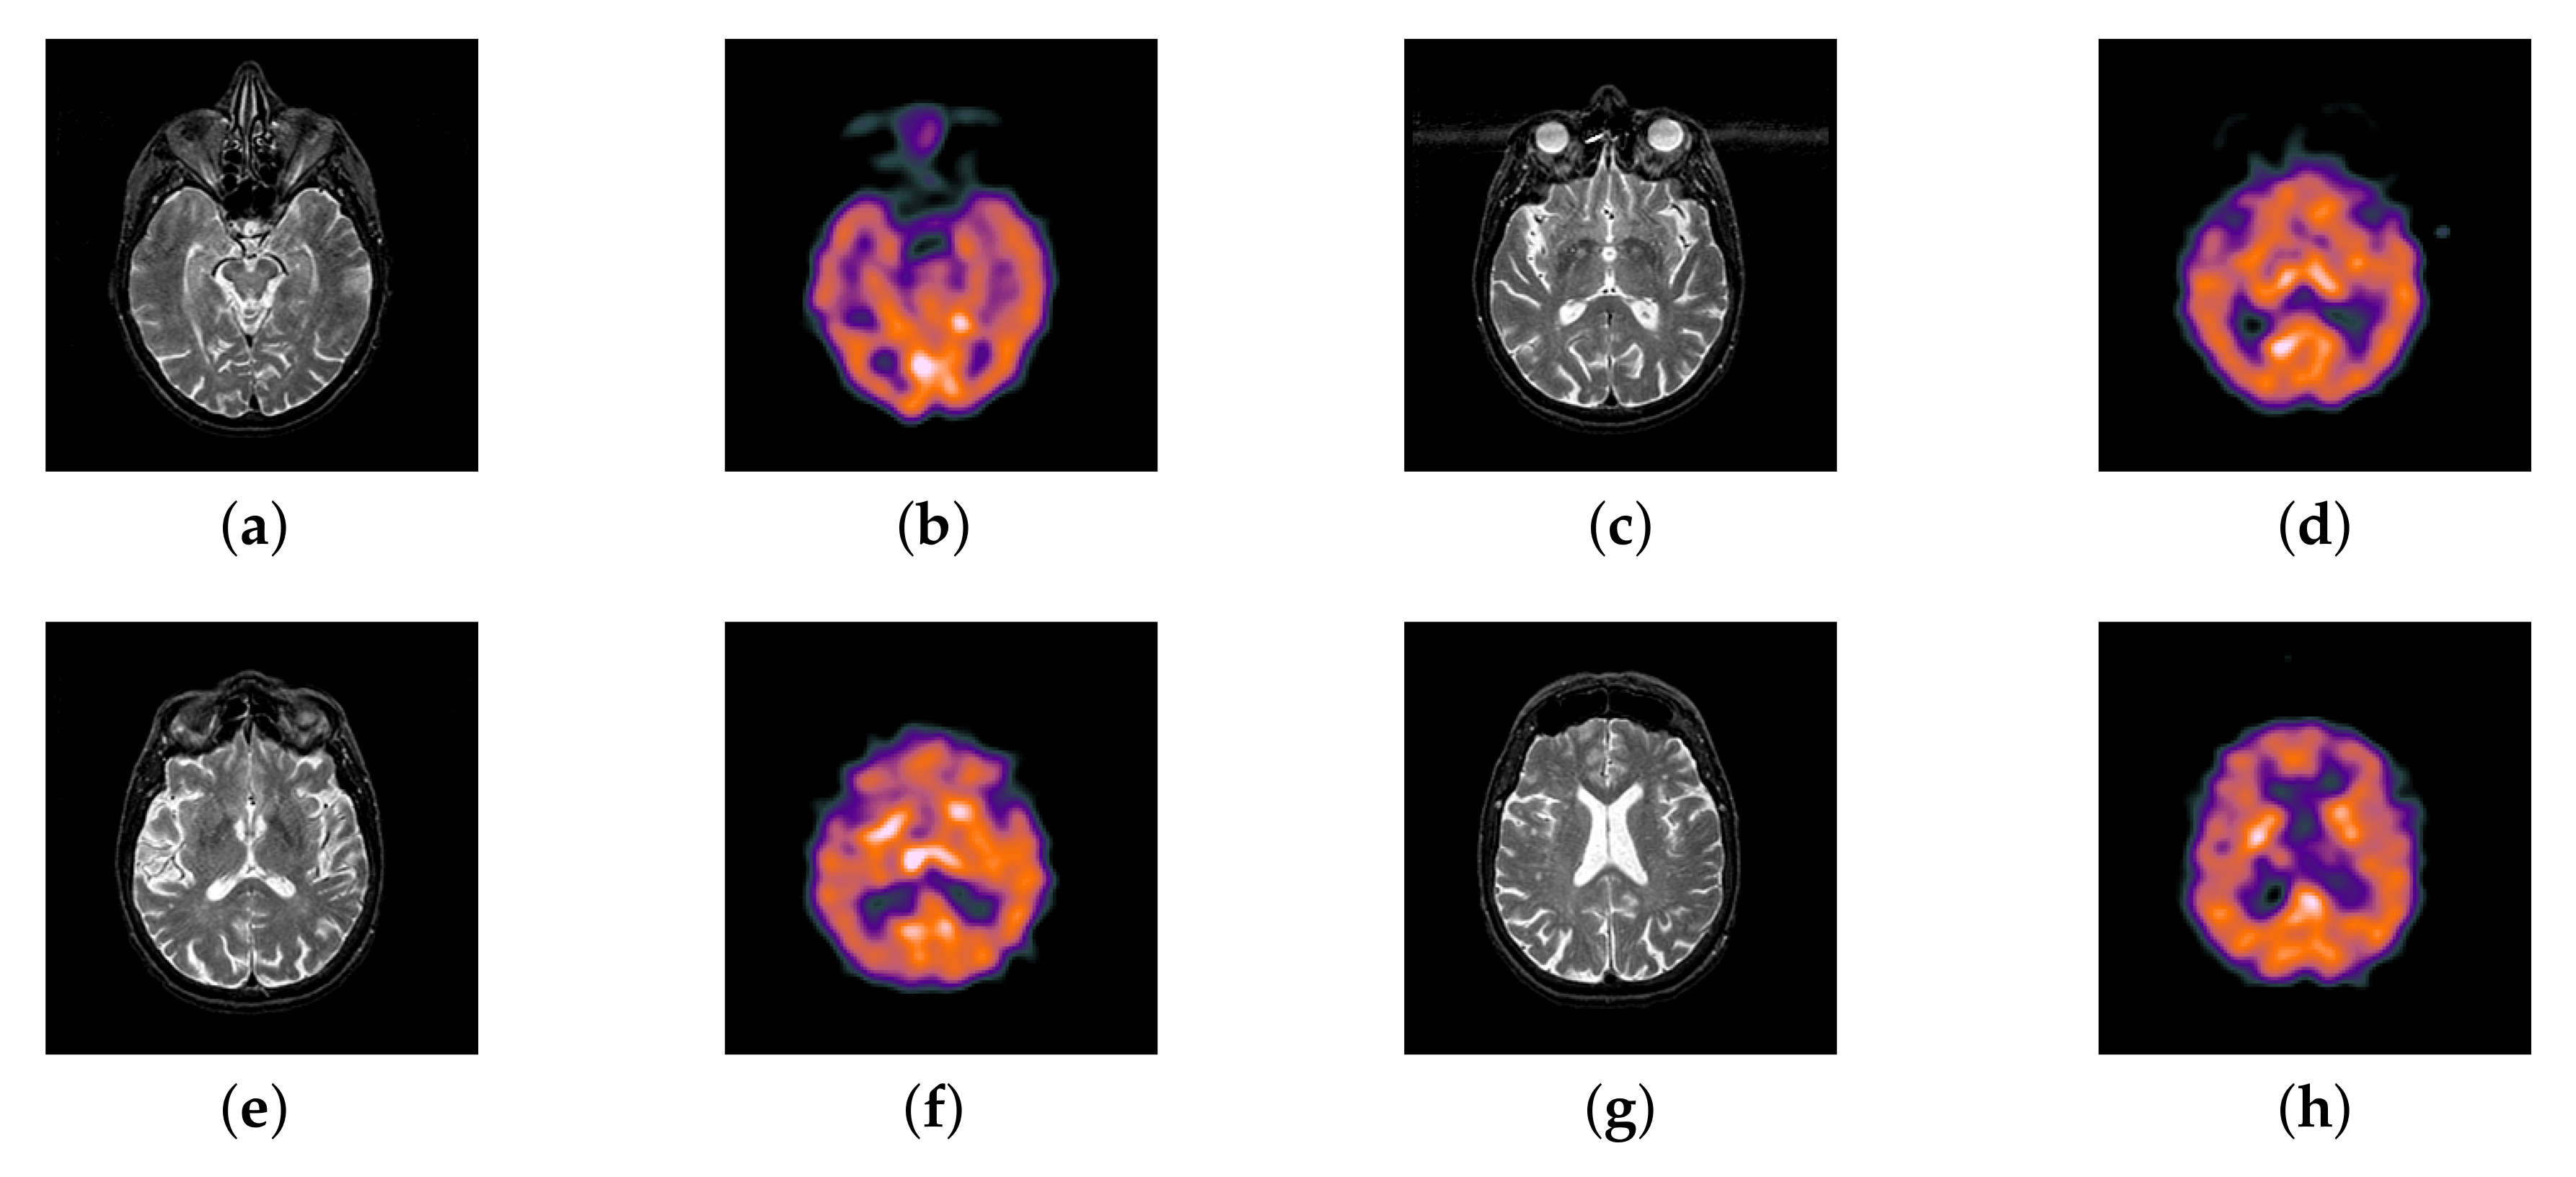

Fludeoxyglucose (FDG) image in cancer diagnosis plays an important role; at the same time, it provides the functional information that can predict a pathological reaction to certain types of cancer treatment. As a kind of PET image, FDG image has some features of PET image, such as texture analysis [54] and shape analysis [55], may also provide additional knowledge associated with the treatment outcome. However, FDG image has no structural information, which is its biggest defect. Therefore, the fusion of MRI and FDG can give doctors a great help in the process of cancer diagnosis.

In this section, all FDG images are derived from the normal human brain, but the angle is chosen differently in Figure 24. In Figure 25, Figure 26, Figure 27 and Figure 28, we find that the color information obtained by the image fusion method based on NSCT, DTCWT, and LPSR is better preserved, but the structure information is lost more. The fusion image based on GFF, IGM, and FusionCNN method retains the complete structure information in the MRI image, but the color obtained from the FDG image is distorted. The image color information obtained by DDcGAN fusion method is too bright, resulting in unclear color area details and low contrast of color region. In contrast, the image obtained by our algorithm has moderate brightness of color information, complete structure information, and complete biological detail information.

Figure 24.

Four pairs of MRI-Fludeoxyglucose (FDG) source images: (a,c,e,g) are MRI images; (b,d,f,h) are FDG images.

Figure 25.

Fused medical images obtained by different algorithms (Figure 24a,b): (a) DTCWT, (b) GFF, (c) NSCT, (d) LPSR, (e) IGM, (f) FusionCNN, (g) DDcGAN, and (h) FusionNet.

Figure 26.

Fused medical images obtained by different algorithms (Figure 24c,d): (a) DTCWT, (b) GFF, (c) NSCT, (d) LPSR, (e) IGM, (f) FusionCNN, (g) DDcGAN, and (h) FusionNet.

Figure 27.

Fused medical images obtained by different algorithms (Figure 24e,f): (a) DTCWT, (b) GFF, (c) NSCT, (d) LPSR, (e) IGM, (f) FusionCNN, (g) DDcGAN, and (h) FusionNet.

Figure 28.

Fused medical images obtained by different algorithms (Figure 24g,h): (a) DTCWT, (b) GFF, (c) NSCT, (d) LPSR, (e) IGM, (f) FusionCNN, (g) DDcGAN, and (h) FusionNet.